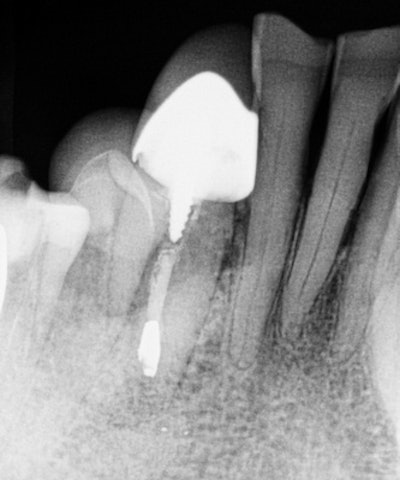

The second case is of a 70-year-old patient of record who called early on a Monday morning and stated that he was up all night in severe pain. His chief complaint was pain in the lower right quadrant. On examination, I determined that his swelling spanned from the lower right lateral incisor to the second premolar, with concomitant pain to palpation and percussion. A Schick 33 (Sirona) periapical radiograph was taken, revealing the lower right canine as the culprit.

A previously treated endodontic tooth was failing. On initial review, I considered dismantling and retreating. The fill appeared to be short of the apex, but because of the extent of the swelling and level of pain, I wanted to evaluate in an enhanced 3D scan. The imaging led to my referral of this patient to an oral surgeon for an apicoectomy in an effort to retain this tooth.

Interestingly, the tangential view was similar to the periapical view, but the cross-sectional view influenced my decision.

Looking carefully, one can see that the fill was well-done, and the buccal lingual tooth length was not the same in the horizontal plane. I did not feel that retreatment could improve this situation. An extraction and bone graft would not be the first choice, as his dentition was extremely crowded in this area. Crown and bridge also would be challenging to say the least.